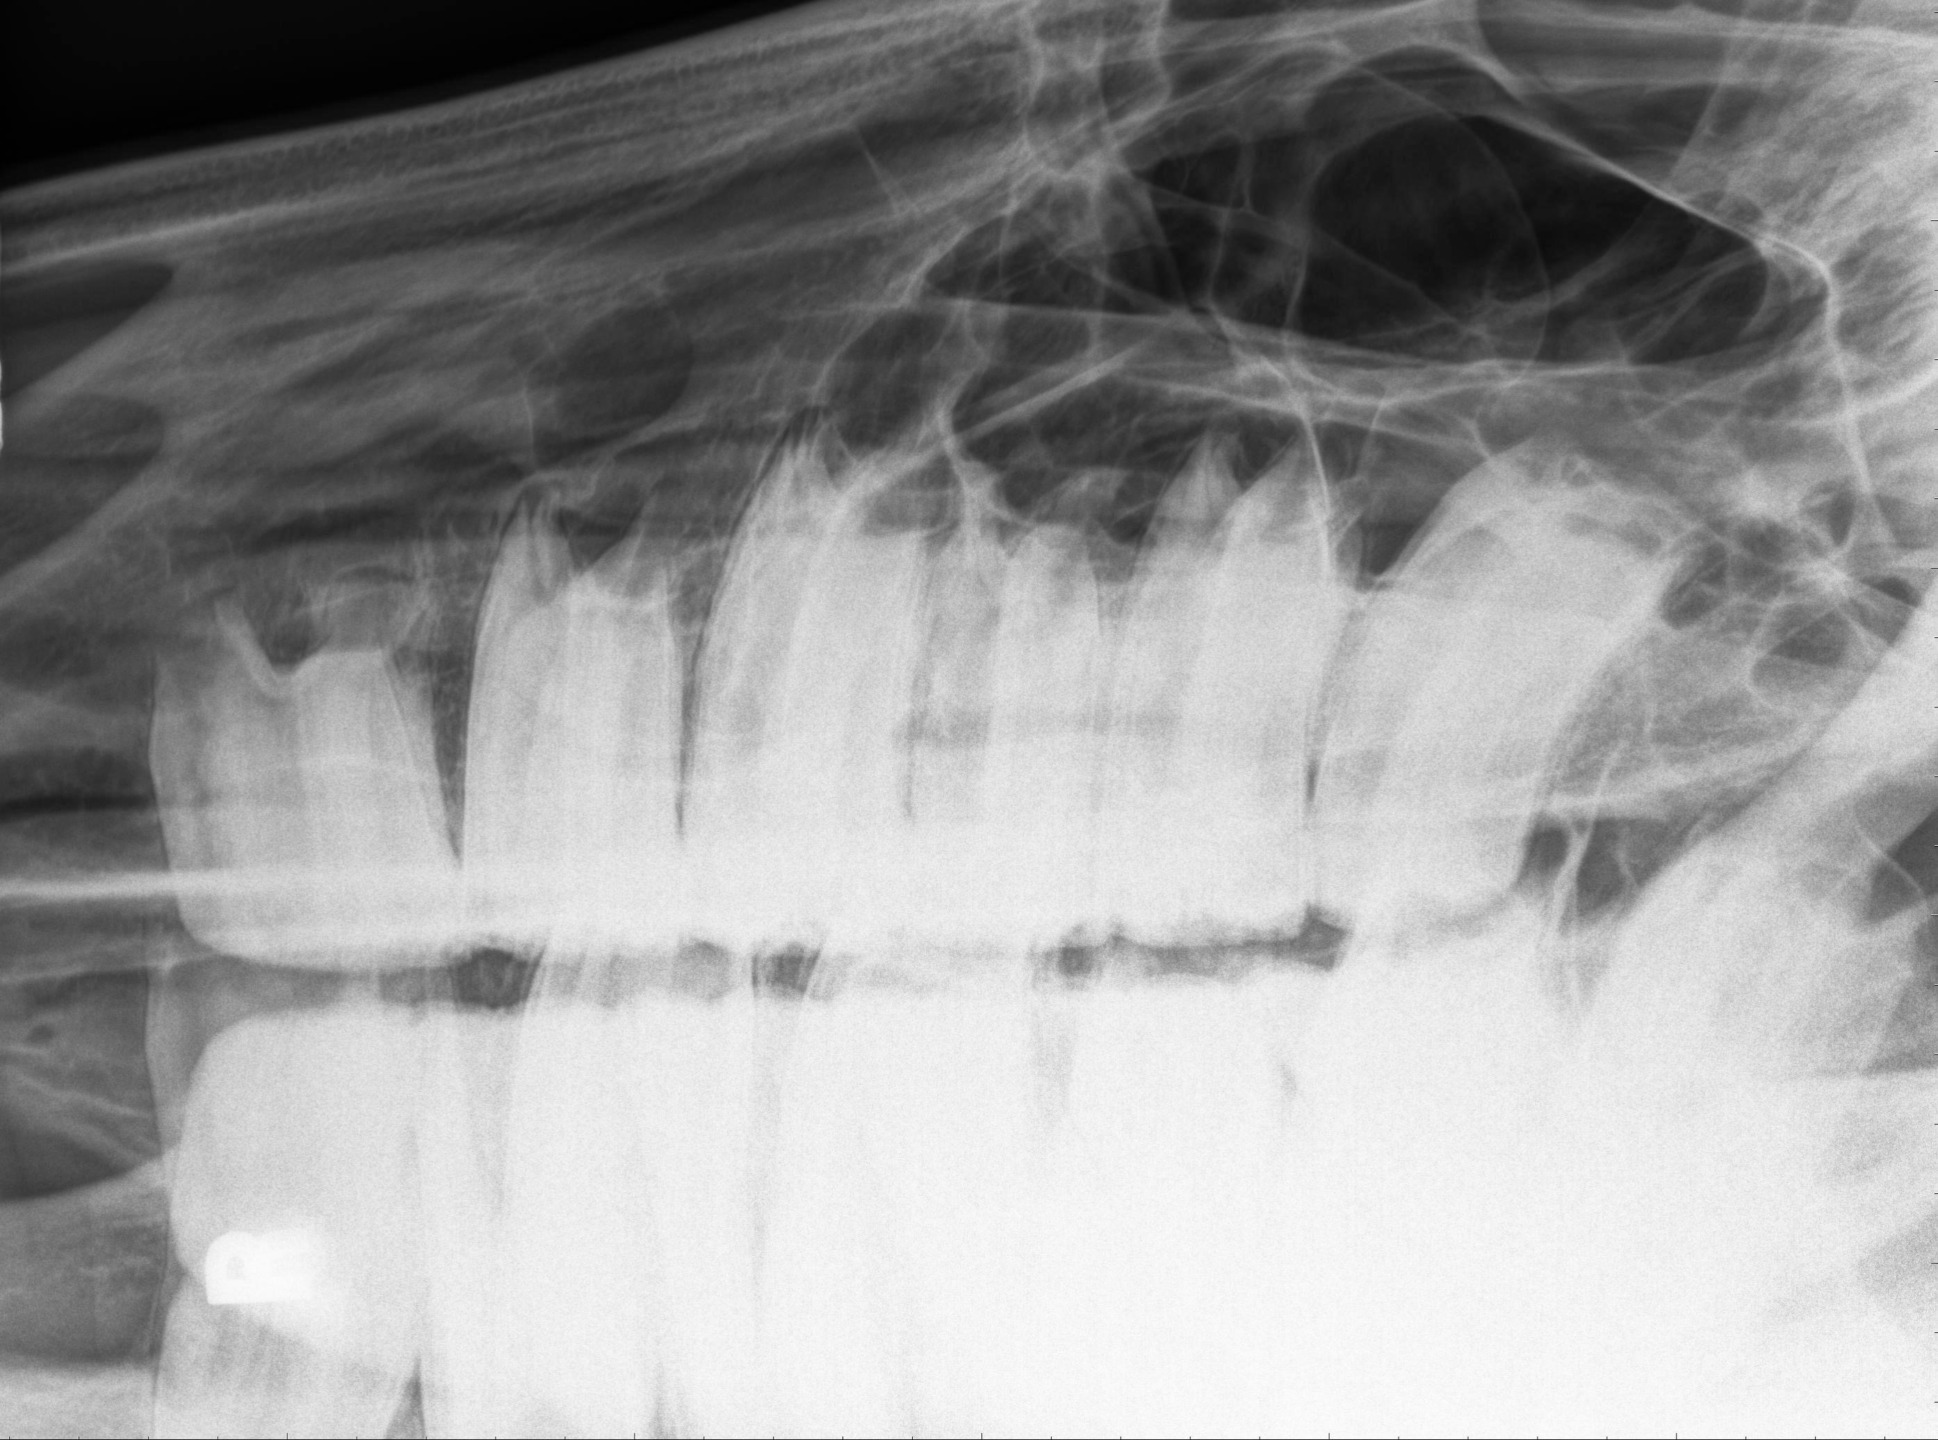

La radiografia è lo strumento di primo livello per indagare anomalie dentali o sinusali già sospettate durante l’esame clinico. Essa consente di visualizzare strutture ossee e dentarie come la lamina dura, l’osso alveolare, le arcate mandibolari e mascellari, le cavità nasali e i seni paranasali.

La testa del cavallo, grazie alla presenza combinata di aria e osso, offre un buon contrasto radiografico. Tuttavia, la sua complessità anatomica può rendere difficile individuare lesioni sottili. È quindi essenziale effettuare l’esame con il cavallo sedato per evitare movimenti.

Le radiografie extraorali con la bocca chiusa sono comunemente usate per studiare i denti posteriori e i seni. Le viste standard includono:

- Laterale (LAT): utile per valutare seni e occlusione.

- Bocca aperta: riduce le sovrapposizioni, migliora la visualizzazione delle corone.

- Obliqua dorso-ventrale: consente di esaminare le radici dei molari superiori e i seni mascellari.

- Dorso-ventrale (DV): buona per visualizzare le strutture centrali del cranio.

Per i denti mandibolari, la presenza del muscolo massetere e lo spazio stretto tra le branche mandibolari rendono l’acquisizione più difficile. In questo caso, si preferisce una proiezione obliqua ventro-dorsale per migliorare la visualizzazione delle radici.

Interpretazione radiografica: cosa cercare

Conoscere l’anatomia radiografica è essenziale per un’interpretazione corretta. Tra i punti chiave:

- Apici dentali: la parte terminale della radice

- Lamina dura: osso compatto che circonda la radice

- Legamento parodontale: sottile linea radiotrasparente tra dente e osso

- Cresta alveolare: proiezione ossea tra denti adiacenti

Segni radiografici di malattia includono:

- Lucenza periapicale (segno di ascesso apicale)

- Apici ottusi o deformati (segno di infiammazione cronica)

- Ispessimento irregolare della lamina dura

- Allargamento dello spazio parodontale

- Segni di sinusite mascellare (opacità diffusa e livelli fluidi)

- Riassorbimento osseo alveolare (segno di parodontite avanzata)

La radiografia è uno strumento diagnostico imprescindibile per il monitoraggio e il trattamento delle patologie orali e sinusali nel cavallo.